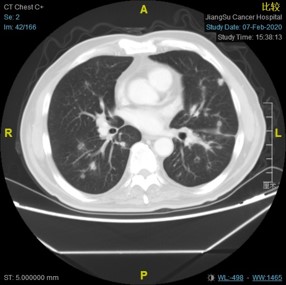

2015-05-08 CT示:左下肺结节,较前稍增大,实性成分较前稍增多,拟转移可能。

2015-09-23CT:左下肺结节,较前增大,拟转移;结肠术区肠系膜结构致密,见斑片索条影,较前变化不大,仍考虑为术后改变;盆腔积液较前减少。

3、左下肺见片状实变影,FDG代谢轻度增高,结合病史,考虑治疗后改变可能,请结合患者既往老片并密切随访。